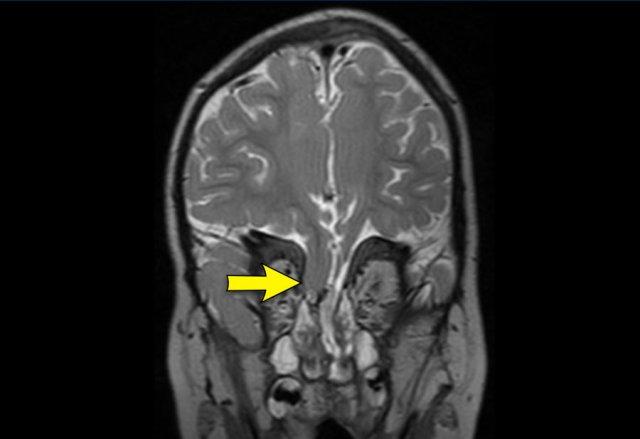

Các hình ảnh thuộc về một bệnh nhân có tăng áp lực nội sọ.

Có hình ảnh thoát vị hạnh nhân tiểu não với tình trạng chèn ép nặng tại vùng nối sọ-cổ.

Hậu quả là hình thành ổ rỗng tủy trải dài toàn bộ chiều dài của tủy sống.